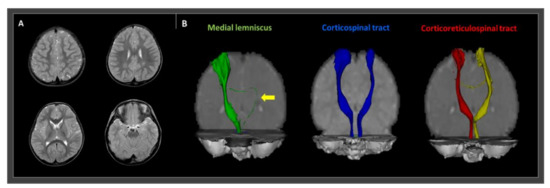

Improvement of Gait Dysfunction after Applying a Hinged Ankle–Foot Orthosis in a Hemiplegic Cerebral Palsy Patient with Disrupted Medial Lemniscus: A Case Report

by Su Min Son and Min Cheol Chang

Children 2021, 8(2), 81; https://doi.org/10.3390/children8020081 - 25 Jan 2021

Cited by 3 | Viewed by 3104

We describe the successful application of hinged ankle−foot orthoses (AFOs) in a cerebral palsied (CP) patient with gait instability due to a disrupted medial lemniscus (ML). The patient was a 27-month-old male CP child with gait instability who presented with reduced knee flexion [...] Read more.

We describe the successful application of hinged ankle−foot orthoses (AFOs) in a cerebral palsied (CP) patient with gait instability due to a disrupted medial lemniscus (ML). The patient was a 27-month-old male CP child with gait instability who presented with reduced knee flexion and ankle dorsiflexion, with severe genu recurvatum on his right lower extremity during gait. The patient had no motor weakness or spasticity. Conventional magnetic resonance imaging (MRI) revealed no definite abnormal lesion. However, diffusion tensor tractography (DTT) showed disruption of the left ML, consistent with right hemiplegic symptoms. The integrity of the major motor-related neural tracts, including the corticospinal and corticoreticulospinal tracts, was preserved. We considered that the patient’s abnormal gait pattern was related to the disrupted ML state. We applied hinged AFOs, which immediately resulted in a significantly stabilized gait. The angles of knee flexion and ankle dorsiflexion increased. Our findings indicate that the application of hinged AFOs could be a useful therapeutic option for CP patients with gait instability related to ML disruption. In addition, we showed that DTT is a useful tool for identifying the causative brain pathology in CP patients, especially when conventional brain MRIs show no specific lesion. Full article